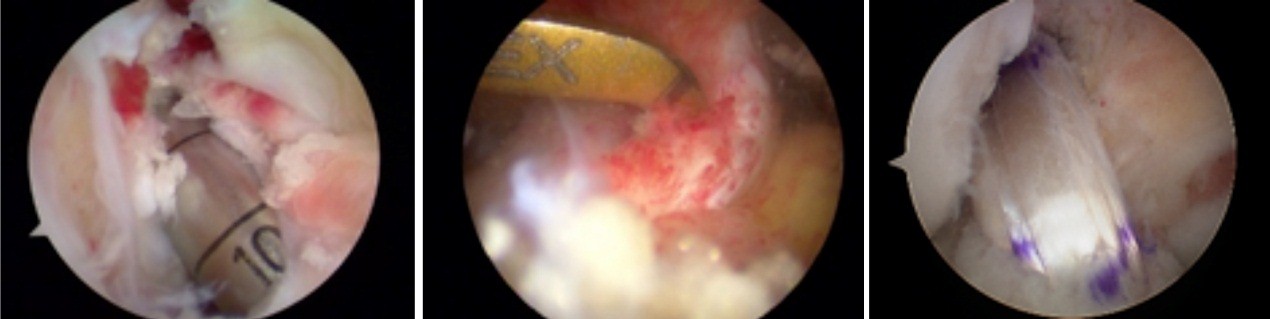

开展关节镜下交叉韧带单、双股解剖重建技术、膝关节多韧带损伤的一期修复重建术、半月板缝合技术、骨软骨移植技术、同种异体移植治疗交叉韧带损伤、双隧道重建交叉韧带、肩关节镜下肩袖修补和SLAP损伤修补术,及肘、踝、腕、髋关节镜术。专业运动员伤病诊治技术、股骨髋臼撞击综合症、股骨头坏死阶梯治疗技术、骨软骨移植技术

关节镜清理、软骨移植修复

膝关节镜-半月板损伤

膝关节镜-前交叉韧带重建

膝关节镜-关节内游离体